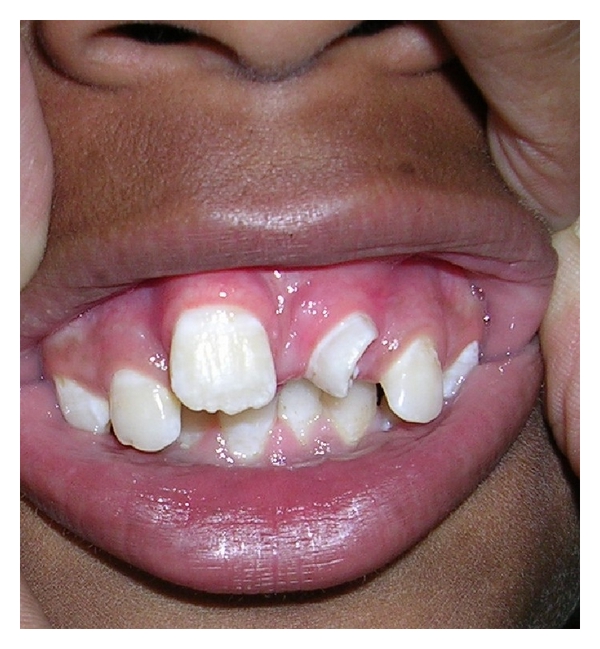

A 13-years-old child reported with complaint of abnormally erupted tooth in maxillary anterior region (Figure 1). Intraoral examination revealed partial horizontally erupted tooth in left central incisor region. Only incisal and part of middle one third of the abnormally erupted tooth was visible. The lingual surface appeared abnormal with infolding of mesial and distal edges towards centre creating a central depressed area (Figure 2).